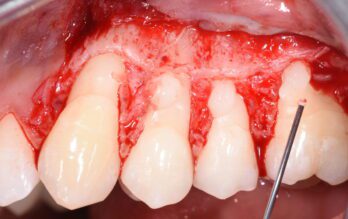

Application of Perisolv

“Cases of dr. V. Iorio-Siciliano”